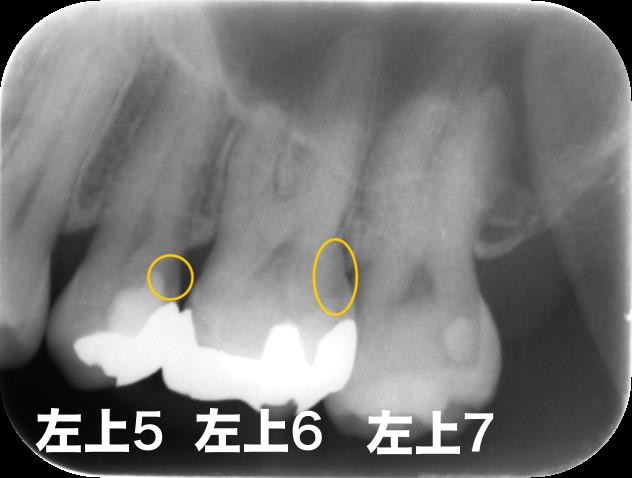

上顎洞炎マイクロスコープ診療根管治療/再根管治療

他院にて詰め物を入れたが違和感が治まらず、神経が死んでしまっていた患者様 感染根管治療にて治療

| 治療方法 |

感染根管治療 |